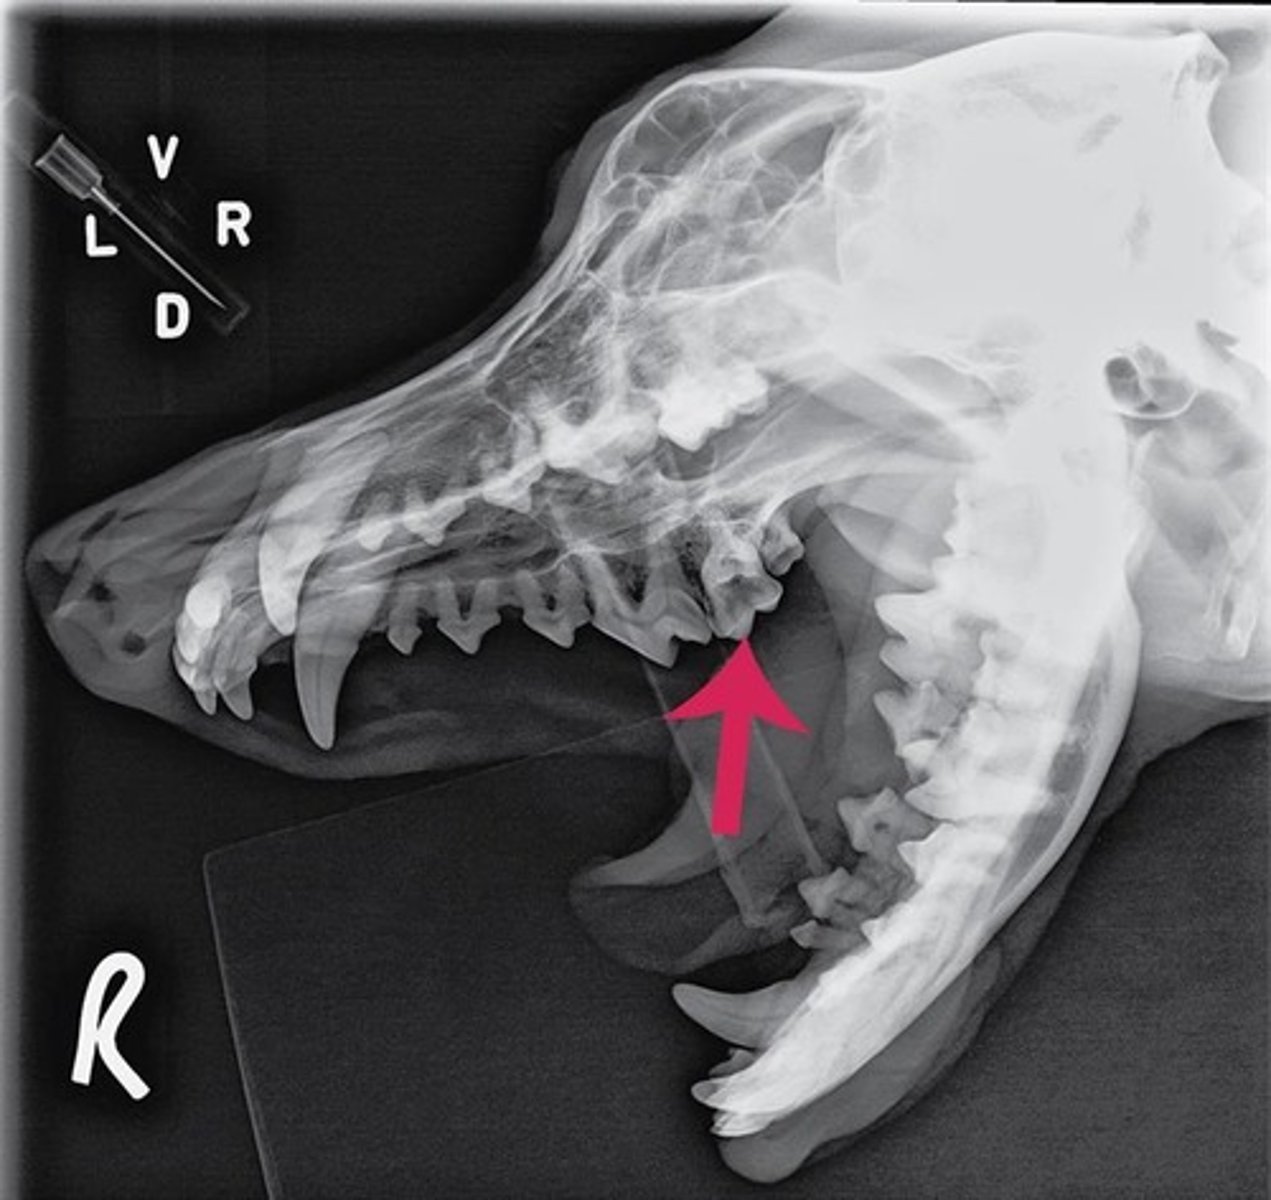

Using the Triadan system, enter the three-digit number that corresponds to the tooth pointed at by the arrow.

309

Using the Triadan system, enter the three-digit number that corresponds to the tooth pointed at by the arrow.

404

Using the Triadan system, enter the three-digit number that corresponds to the tooth highlighted.

704

Canine is #04 and in quadrant 3, so add 4 to the quadrant to get 7 and that equals 704

Triadan number for lower left deciduous canine.